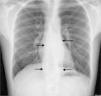

A 21-year-old man presented with sloping cervical mass. He was diagnosed with lymphadenitis caused by tuberculosis and taking antituberculosis drugs for 5 months. He received isoniazid, rifampin, ethambutol, and morfosinamide for 2 months and then continue with isoniazid and rifampin. At the end of second month the leakage stopped, but one month later, leakage from the lymphadenitis reoccurred. He had night sweats, and weight loss that never decreased with antibiotherapy. He presented with serious back pain since last year. He had no history of lung tuberculosis, but his family members presented with tuberculosis. His father had lung tuberculosis whereas his mother and sister had tuberculosis lymphadenitis. All of them received standard antituberculosis therapy and their therapy was successfully completed. In our patient computerized tomography (CT) scanning of thorax demonstrated a Pott abscess formation, nearly 15cm length between thoracic vertebrae 5 and 11, which may be easily misdiagnosed as an aortic aneurism with the imagination on chest X-ray (Figs. 1 and 2). Microbiological sample was taken with CT-guided biopsy. Only one acid fast bacilli (AFB) was seen with AFB stain. Mycobacterium tuberculosis yielded at Lowenstein–Jensen culture medium. This bacilli was found resistant to all primary antituberculosis therapeutic agents that he was taking. His therapy was stopped and amikacin 1g/day+ethionamide 1000mg/day+cycloserine 1000mg/day+ofloxacin 400mg/day+prazinamide 2500mg/day was given.